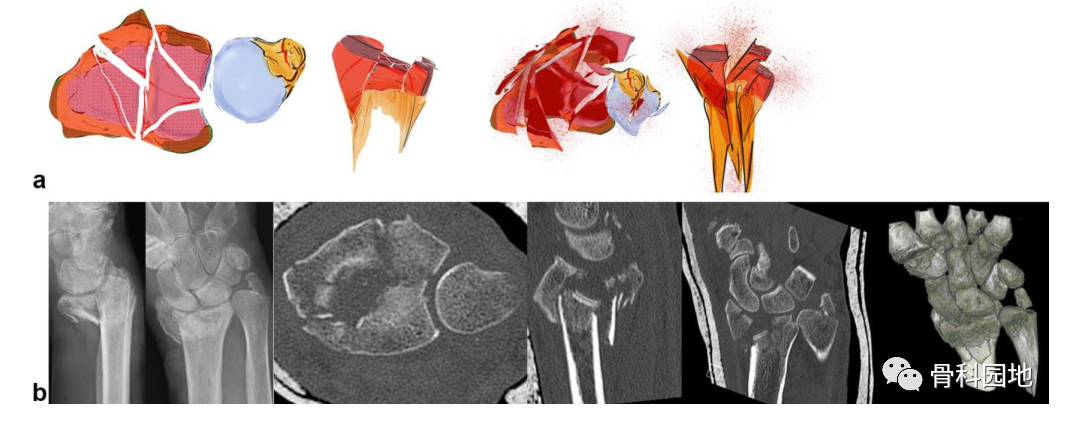

注:轴向作用力可导致关节面的中央塌陷或背侧和掌侧骨折块的爆裂性骨折(见图b)。这个中央关键骨块与轴或腕骨没有韧带连接。有时,它仅在关节面下略微凹陷,容易被忽视。如果这个中央骨块被更深地撞击到桡骨干中,则附着有稳定韧带的背侧和掌侧皮质骨都会像郁金香一样张开(见图 a)

注:这种骨折是桡骨、掌尺骨和背尺骨骨折块的组合(见图 a、b)。每个骨块都是同等重要的关键片段。尽管它们与轴没有连接,但修复对于保持第一腕骨相对于桡骨和尺骨的稳定性至关重要。

3.粉碎性骨折

注:完全破坏桡骨关节面的随机骨折类型(见图a)。关节骨块像浮冰一样自由漂浮在干骺端粉碎区上(见图b)。在当识别关键类型骨折后,对选择理想的治疗方案起到了重要的作用(见下表)。